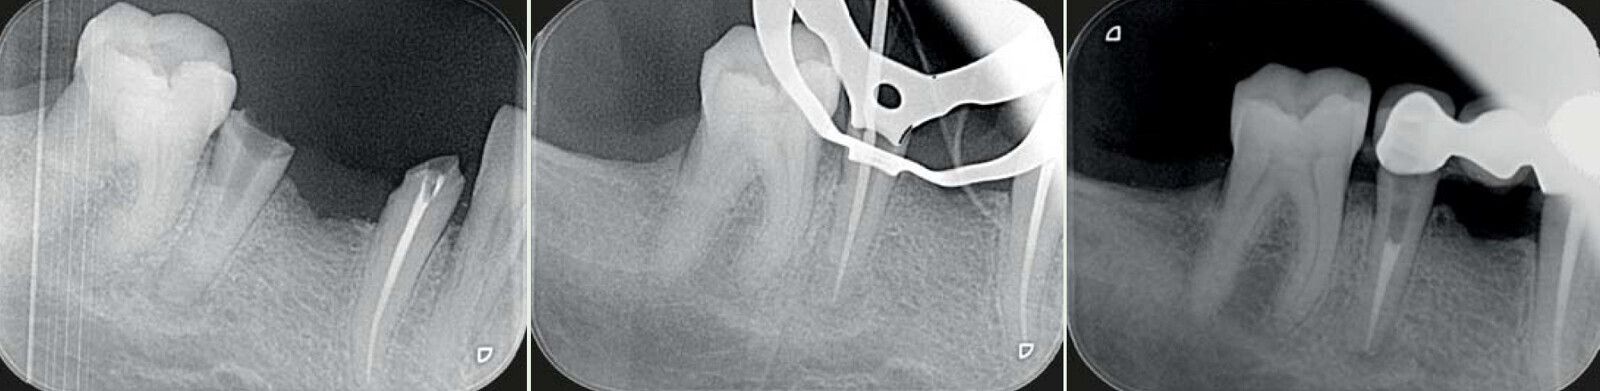

Fig. 7 : les différentes limes du système Genius et séquences utilisées en fonction de du profil radiculaire (c Dr Carlos Spironell Ramos).

Fig. 8 : Cas clinique Dr Camille Bertrand.

Fig. 9 : Cas clinique Dr Camille Bertrand.